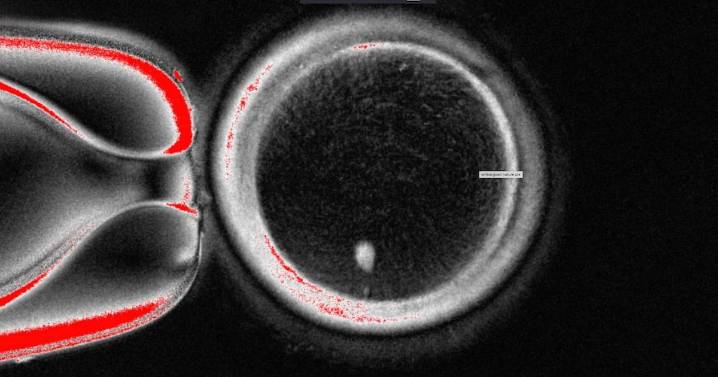

Oregon scientists used human skin cells to create fertilizable eggs, a step in the quest to develop lab-grown eggs or sperm to one day help people conceive.